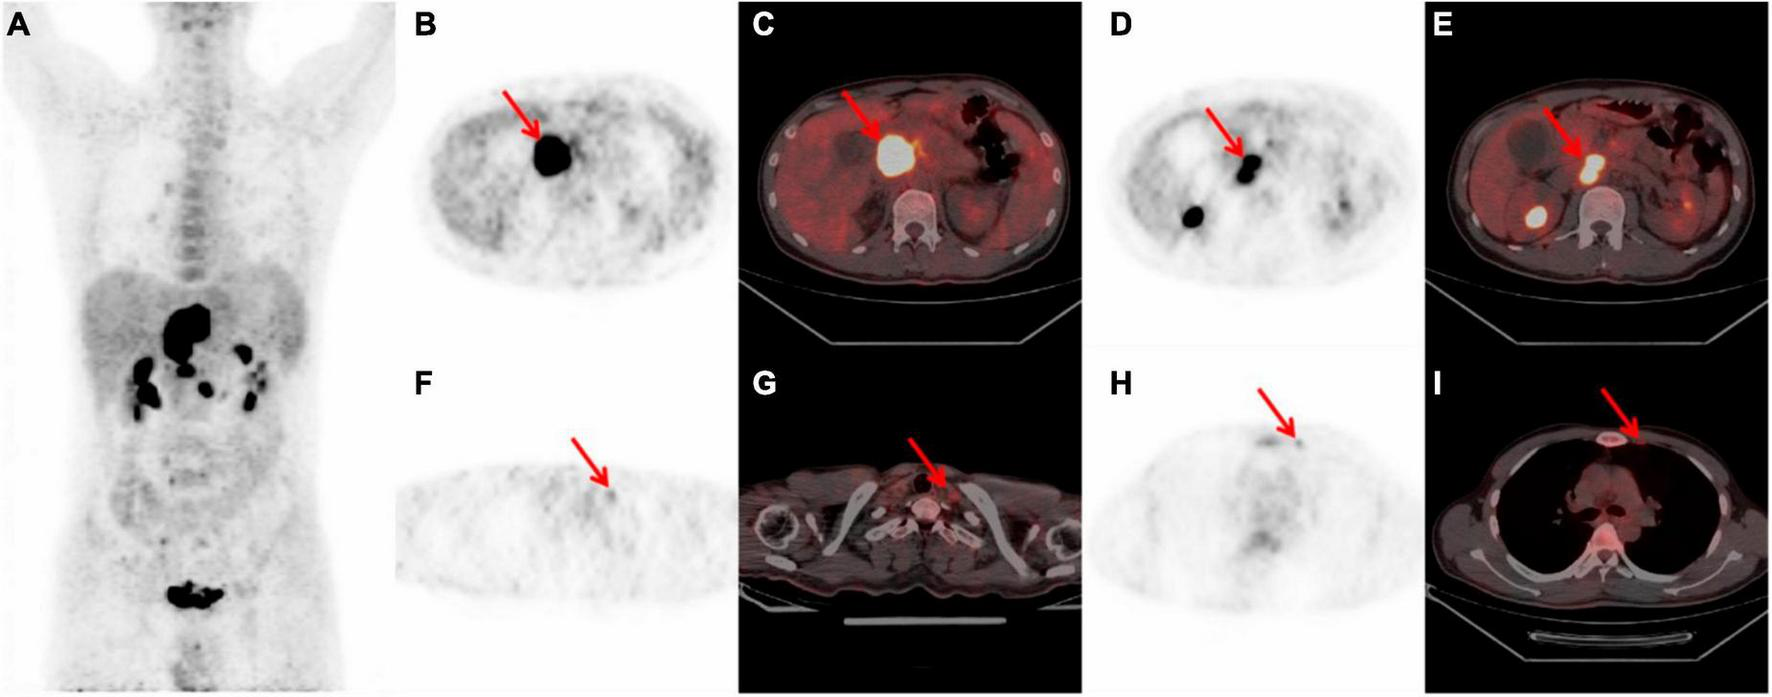

A 70-year-old female presented with a one-month history of unexplained pain below the xiphoid process. She had undergone a myomectomy three decades earlier. Abdominal contrast-enhanced computed tomography (CT) disclosed a slightly hypodense space-occupying lesion within the pancreatic head, accompanied by mild dilatation of the pancreatic duct but without bile duct dilatation. The enhanced scan exhibited relatively modest enhancement. No irregularities emerged during tumor marker assessments, including CA-199, CEA, and CA-125. Laboratory analyses indicated hepatic function impairment (ALT: 539°U/L, AST: 472°U/L, GLD: 140.5°U/L, γ-GT: 615°U/L, ALP: 821°U/L, TBIL: 178.9°μmol/L, DB: 131.5°μmol/L, IBIL: 47.4°μmol/L). In order to pursue further assessment, the patient underwent an 18F-FDG PET/CT examination. The maximum intensity projection (MIP) of the 18F-FDG PET/CT divulged a hypermetabolic lesion within the upper abdomen (Figure 1A). A 9.5 × 8.3 × 7.1 cm irregular lesion situated at the pancreatic head exhibited noteworthy FDG uptake, characterized by a maximal standardized uptake value (SUVmax) of 22.4 (Figures 1B–E). Mild to moderately FDG-avid peripancreatic lymph nodes, displaying indistinct boundaries with the pancreatic mass (Figures 1B–E). Additionally, mildly hypermetabolic retroperitoneal lymph nodes were detected (Figures 1F, G). Subsequent to these findings, the patient underwent a pancreatic tumor biopsy and gastrojejunostomy under general anesthesia. The conclusive histopathological diagnosis unveiled diffuse large B-cell lymphoma of the pancreatic head, identified as the non-germinal center type. Subsequently, this patient commenced a low-dose CHOP chemotherapy regimen combined with rituximab (R-miniCHOP). Encouragingly, the patient displayed commendable tolerance and remained devoid of pronounced adverse reactions. At present, the patient is engaged in the sixth cycle of chemotherapy.

FIGURE 1

Whole body 18F-FDG PET/CT scan of a 70-year-old female with PPL. (A) MIP demonstrated a hypermetabolic lesion in the superior abdominal. (B,C) A 9.5 × 8.3 × 7.1 cm high FDG-avid irregular occupying at the head of the pancreas with a SUVmax 22.4 (red arrow). (D, E) Peripancreatic hypermetabolic enlarged lymph nodes (red arrow). (F, G) Suspicious mild hypermetabolic retroperitoneal lymph node with (red arrow). PPL, primary pancreatic lymphoma; 18F-FDG PET/CT, 18F-fluorodeoxyglucose positron emission tomography/computed tomography; MIP, maximum intensity projection; SUVmax, maximal standardized uptake value.